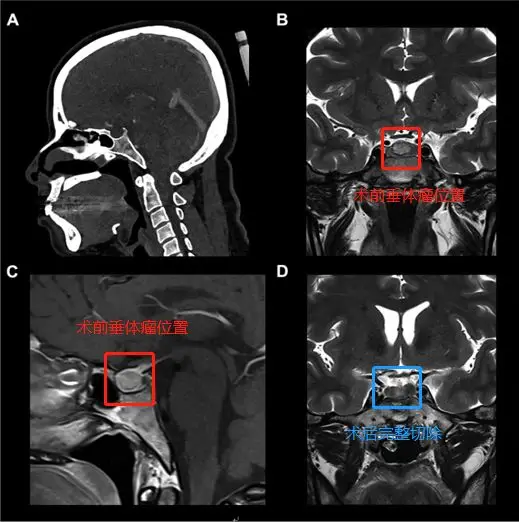

▼37歲女性-蝶鞍中心垂體瘤

37歲女性-蝶鞍中心垂體瘤

術(shù)前(紅色區(qū)域):A、C圖位于蝶鞍中央的9mm垂體微腺瘤。B圖表示計算機斷層掃描儀顯示了蝶竇的鞍周型氣管化。

手術(shù)過程:使用筷子手法進行廣泛的蝶竇切開術(shù),從手術(shù)區(qū)域清除血液并解剖假包膜平面,進而完整地切除腫瘤(不分塊切除,防止腫瘤殘留)

術(shù)后(藍色區(qū)域):D圖顯示垂體瘤被肉眼下完整切除,且完成內(nèi)分泌治療。